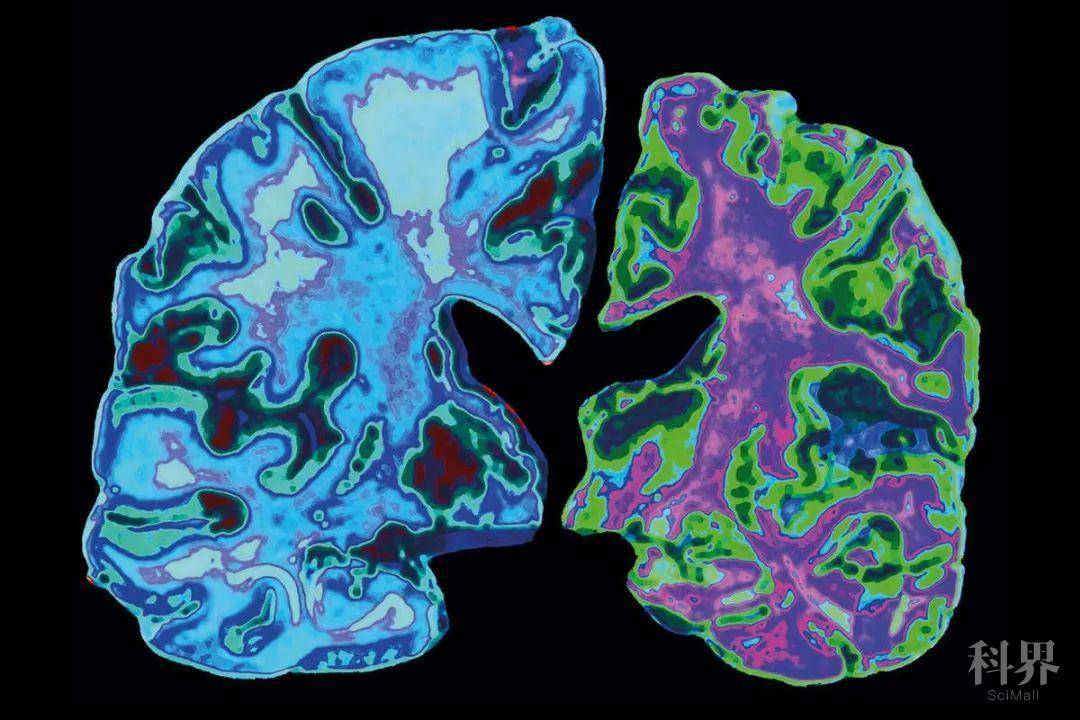

老年痴呆症(AD)是导致痴呆的主要原因。1984年,美国国家神经与交流疾病和卒中研究所-阿尔茨海默病及相关疾病协会(NINCDS-ADRDA)对AD的诊断标准,分为三个诊断级别:明确AD(神经病理诊断)、极可能(probable)AD(临床诊断)、可能possible AD(临床诊断伴有合并症)。

与死后诊断相比,probable AD的临床标准的敏感性和特异性分别为81%和70%。2011年,更新的标准认识到,病理过程在临床症状出现之前就已经开始。磁共振成像(MRI)、正电子发射断层扫描(PET)成像和脑脊液(CSF)检测的使用被更系统地纳入诊断中。引入了额外的几套标准,一套是临床前AD的标准,另一套是AD引起的轻度认知障碍(MCI)的标准,明确将生物标志物(MRI、PET和CSF)纳入诊断。到2018年,推荐了基于淀粉样蛋白("A")、tau("T")和神经变性("N")的生物标志物证据的诊断方案。